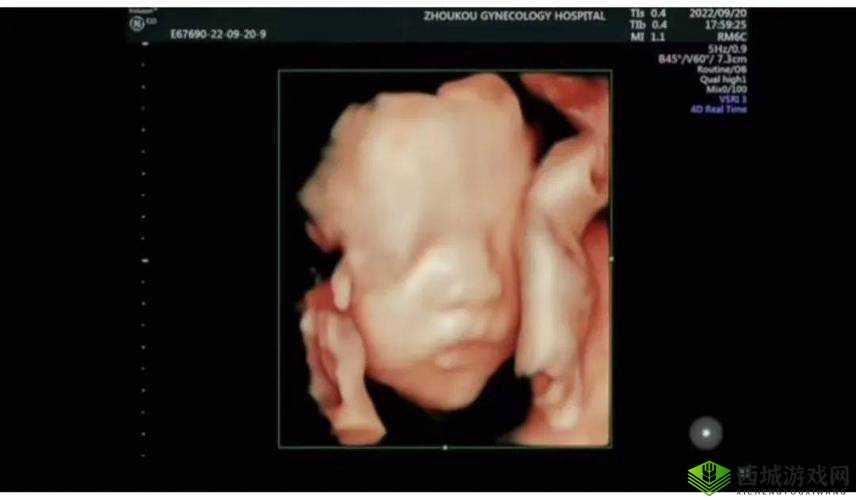

2. 四维彩超:在三维立体成像的基础上增加时间维度,形成动态视频,可清晰显示胎儿的实时动作、面部表情及内脏器官的动态变化。

由于四维彩超的分辨率更高且能捕捉动态画面,医生可通过它发现某些二维B超难以观察到的细节,例如唇腭裂、心脏瓣膜运动异常等。